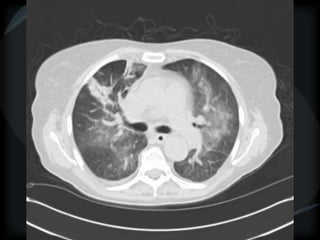

Mosaic CT Patterns

 Ground glass – inflammation/ fibrosis

 airway obstruction (best seen on expiration)

• COPD

• small airway disease

 Vascular obstruction

• chronic thrombotic pulmonary hypertension

• sickle cell disease

• vasculitis